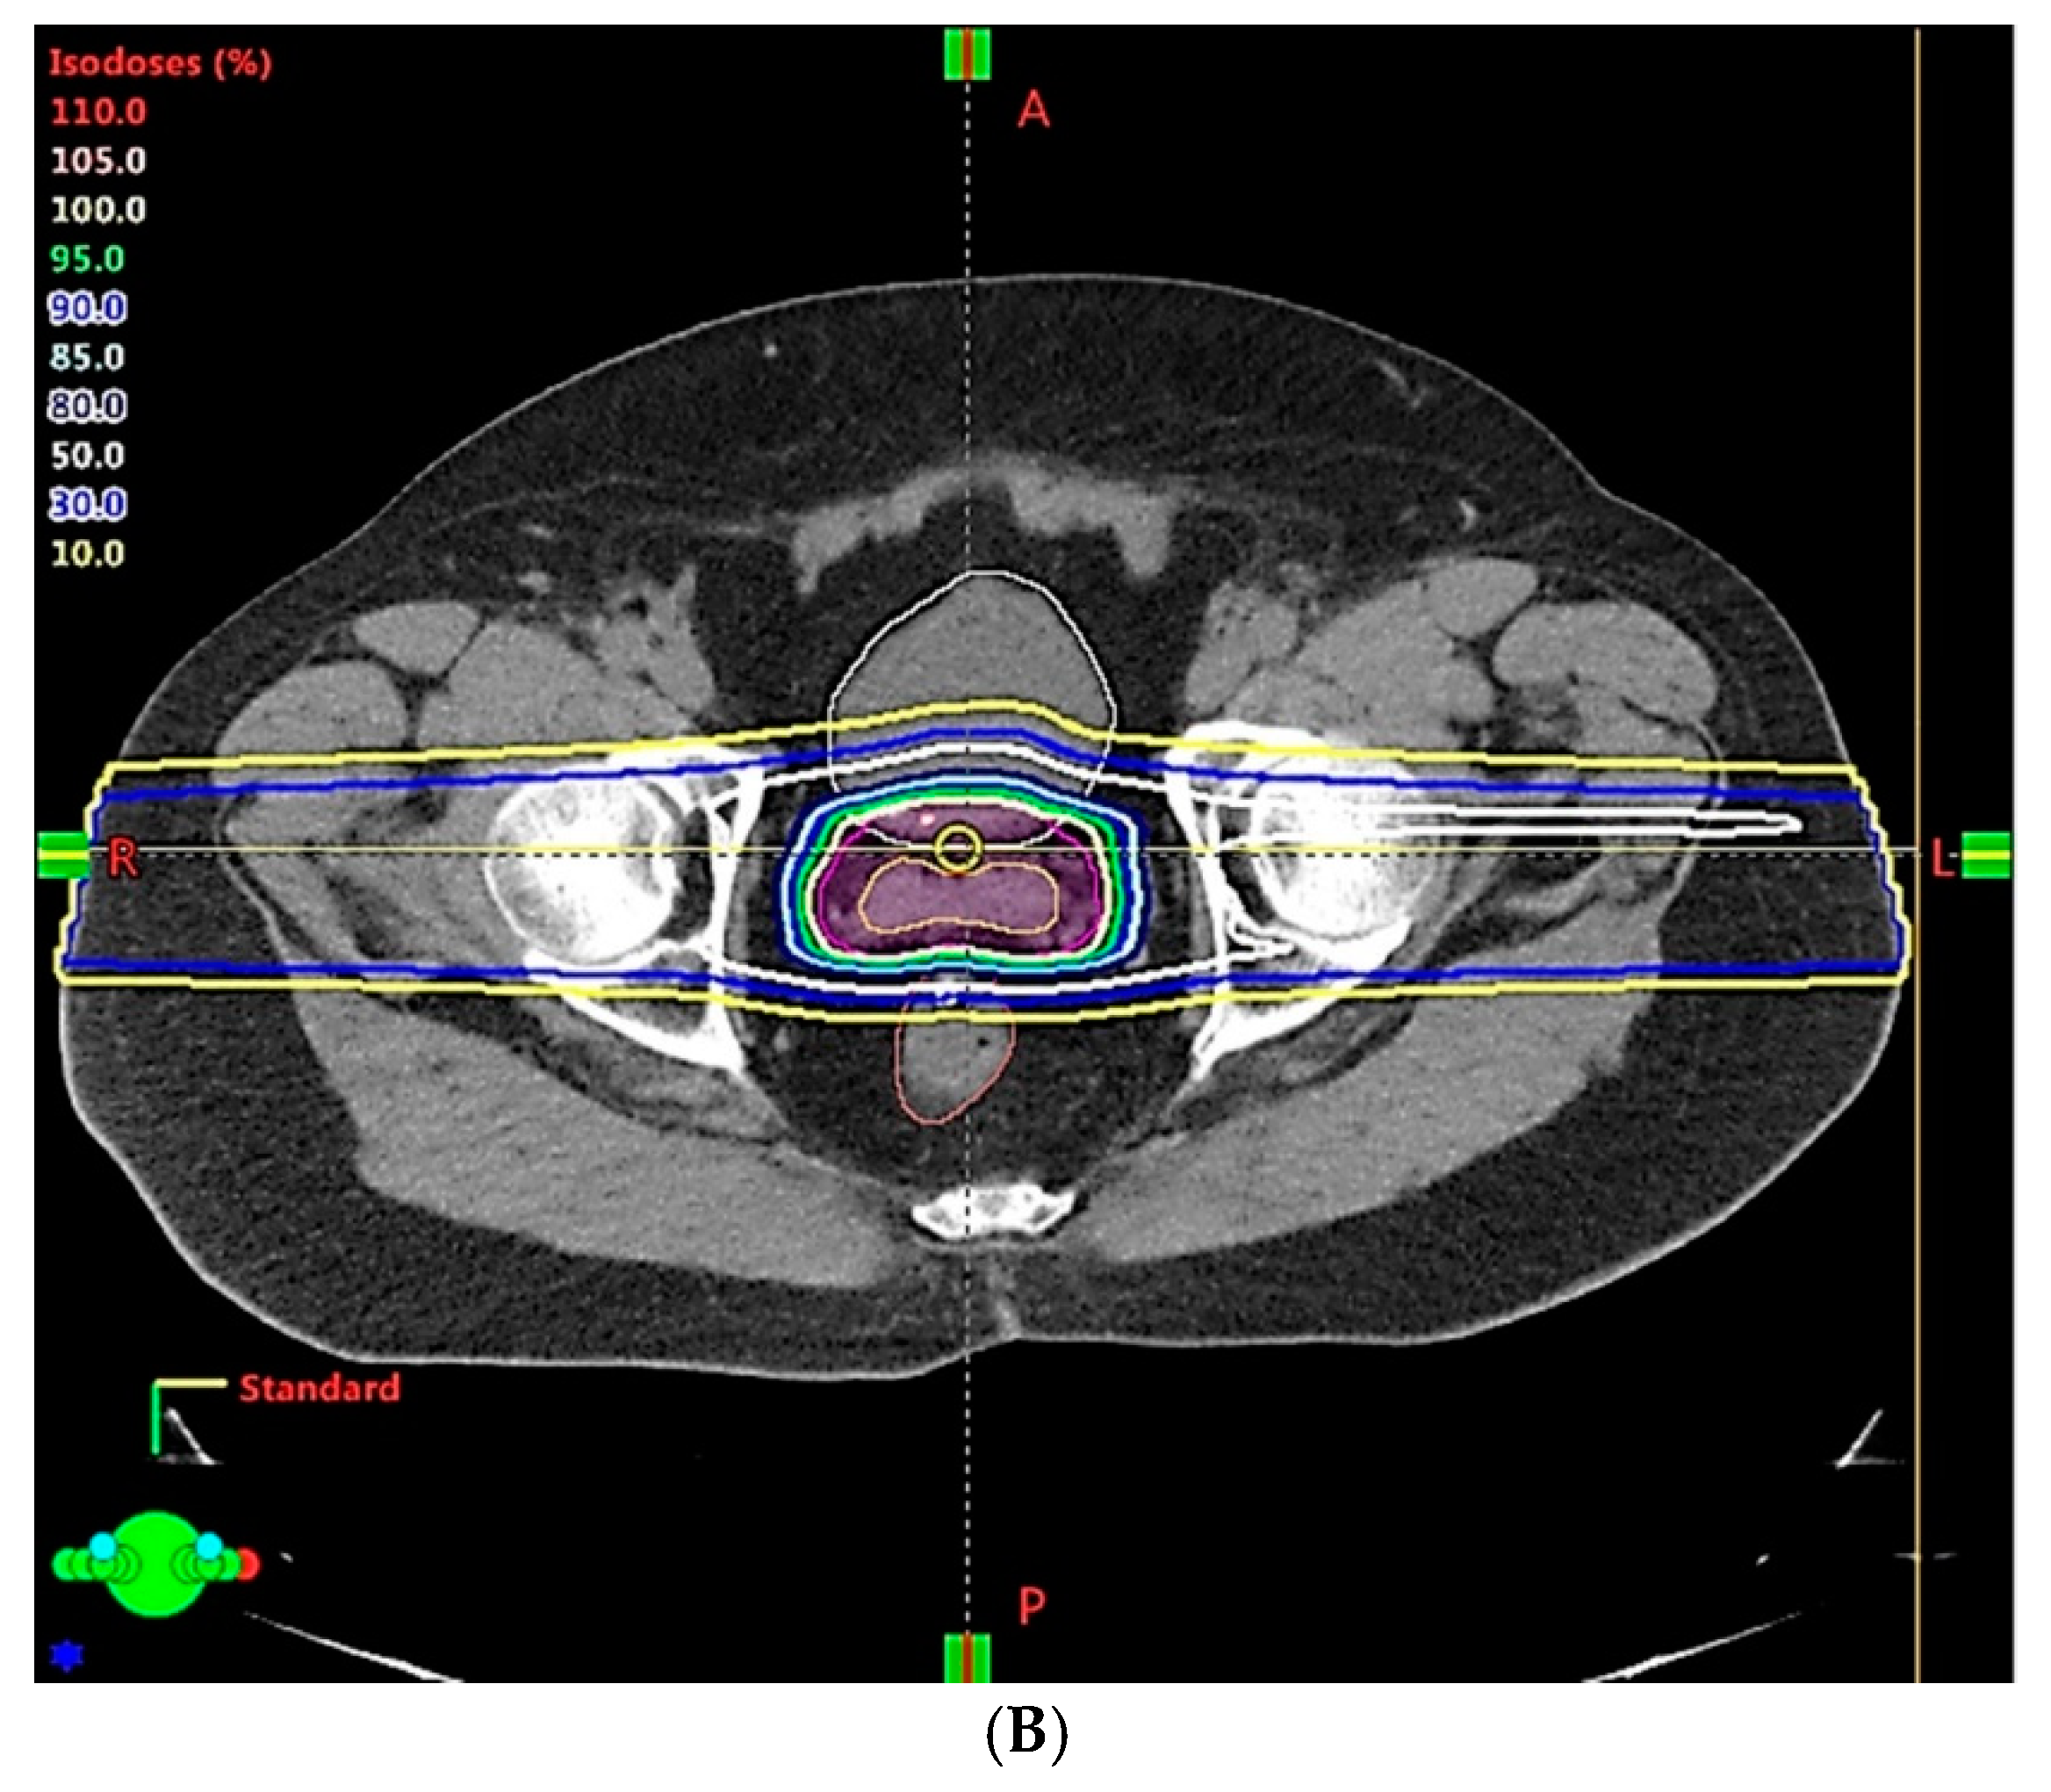

3. Opportunities for Improvement with New Technologies and Innovative Techniques